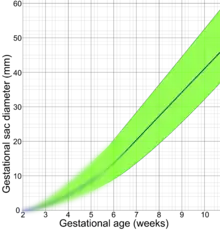

Following are diagrams for estimating gestational age from obstetric ultrasound, by various target parameters:

By gestational sac diameter